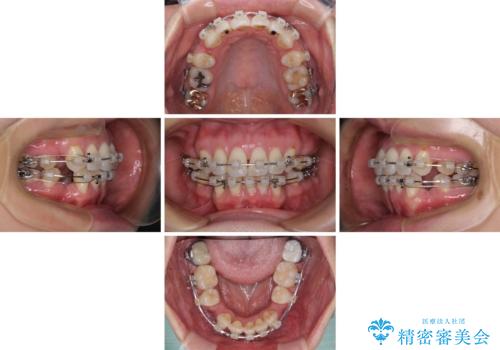

- クリアブラケット

- 治療期間

- 2年3ヶ月